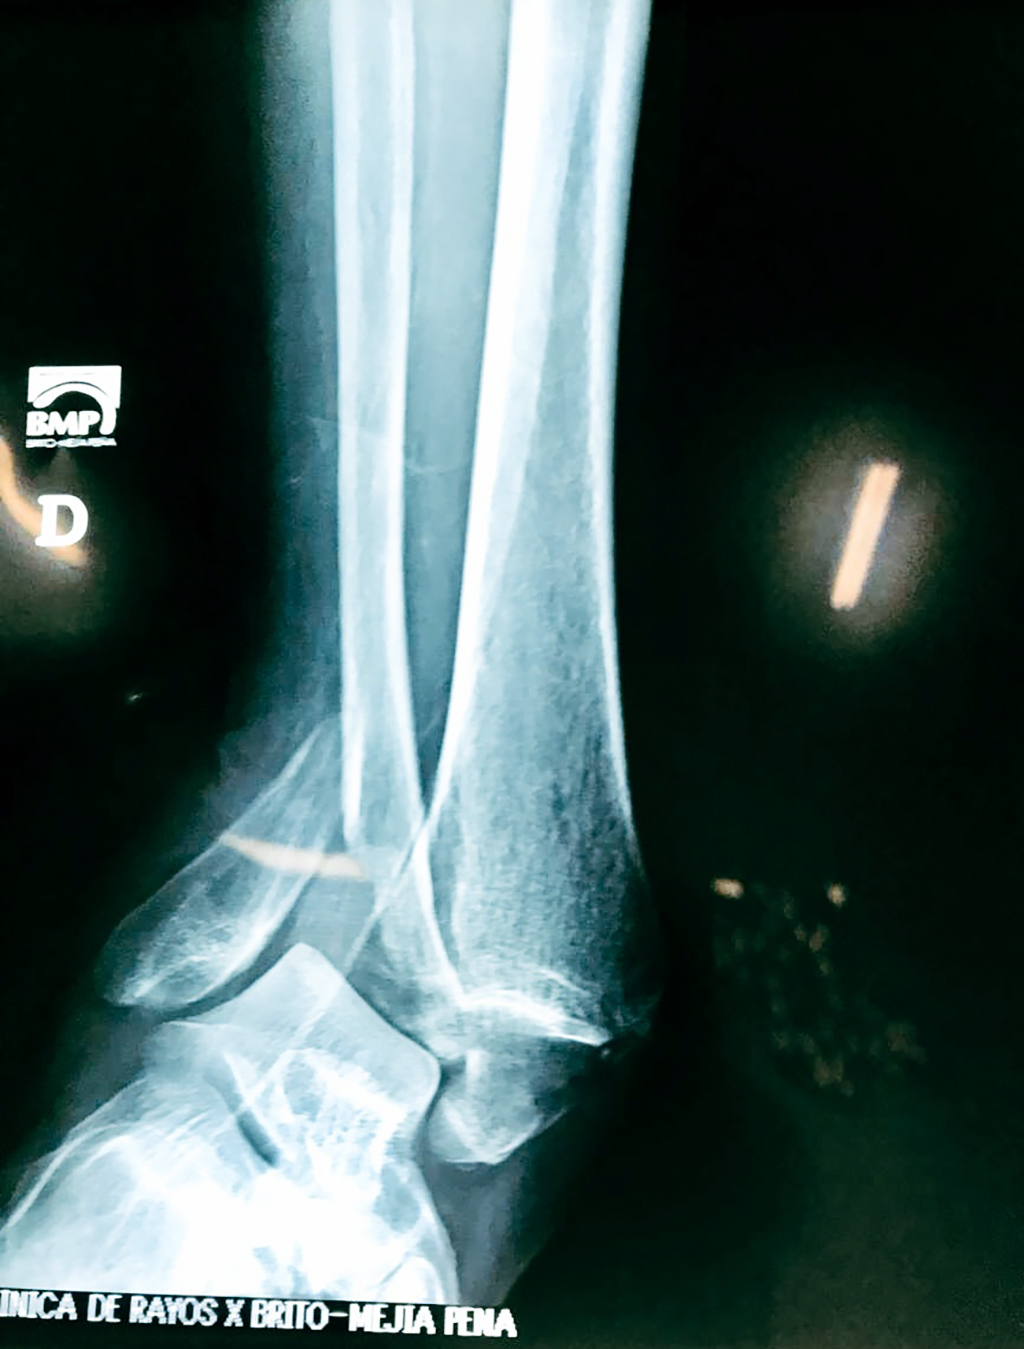

Algunas fracturas de tobillo pueden requerir cirugía si:

- Los extremos de los huesos están desalineados entre sí (desplazados).

- Los tendones o ligamentos (tejidos que sujetan los músculos y los huesos entre sí) están rotos.

Cuando se necesita cirugía, es probable que esta implique el uso de clavijas de metal, tornillos o placas para sostener los huesos en su lugar mientras la fractura se consolida. Los elementos de soporte pueden ser temporales o permanentes.